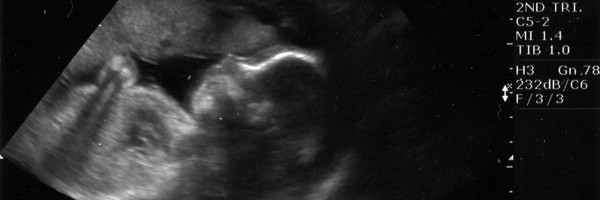

Babies practice crying in the uterus!

Parents who have had so-called 4D ultrasounds might have noticed their baby doing fascinating stuff in the womb, including sucking their thumb, yawning, and making grimaces.